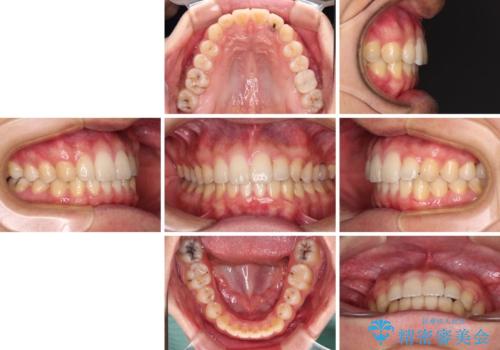

- 前歯のクロスバイトと、大学生のころから放置している虫歯を気にして来院された患者様です。

マウスピースでの矯正治療を希望されていましたが、前歯のクロスバイトは不十分な仕上がりや歯髄壊死などのリスクが高くなるため、術前にワイヤーで大まかに整えてからインビザラインにて矯正治療を行うこととしました。

奥歯の虫歯は抜歯が必要であったので、矯正治療前に抜歯をし、矯正治療と並行してインプラントによる補綴治療を行うこととしました。

当院の特徴は、矯正治療とインプラント補綴治療の担当医が同じ歯科医師であるため、両方の治療を並行して行うことができます。